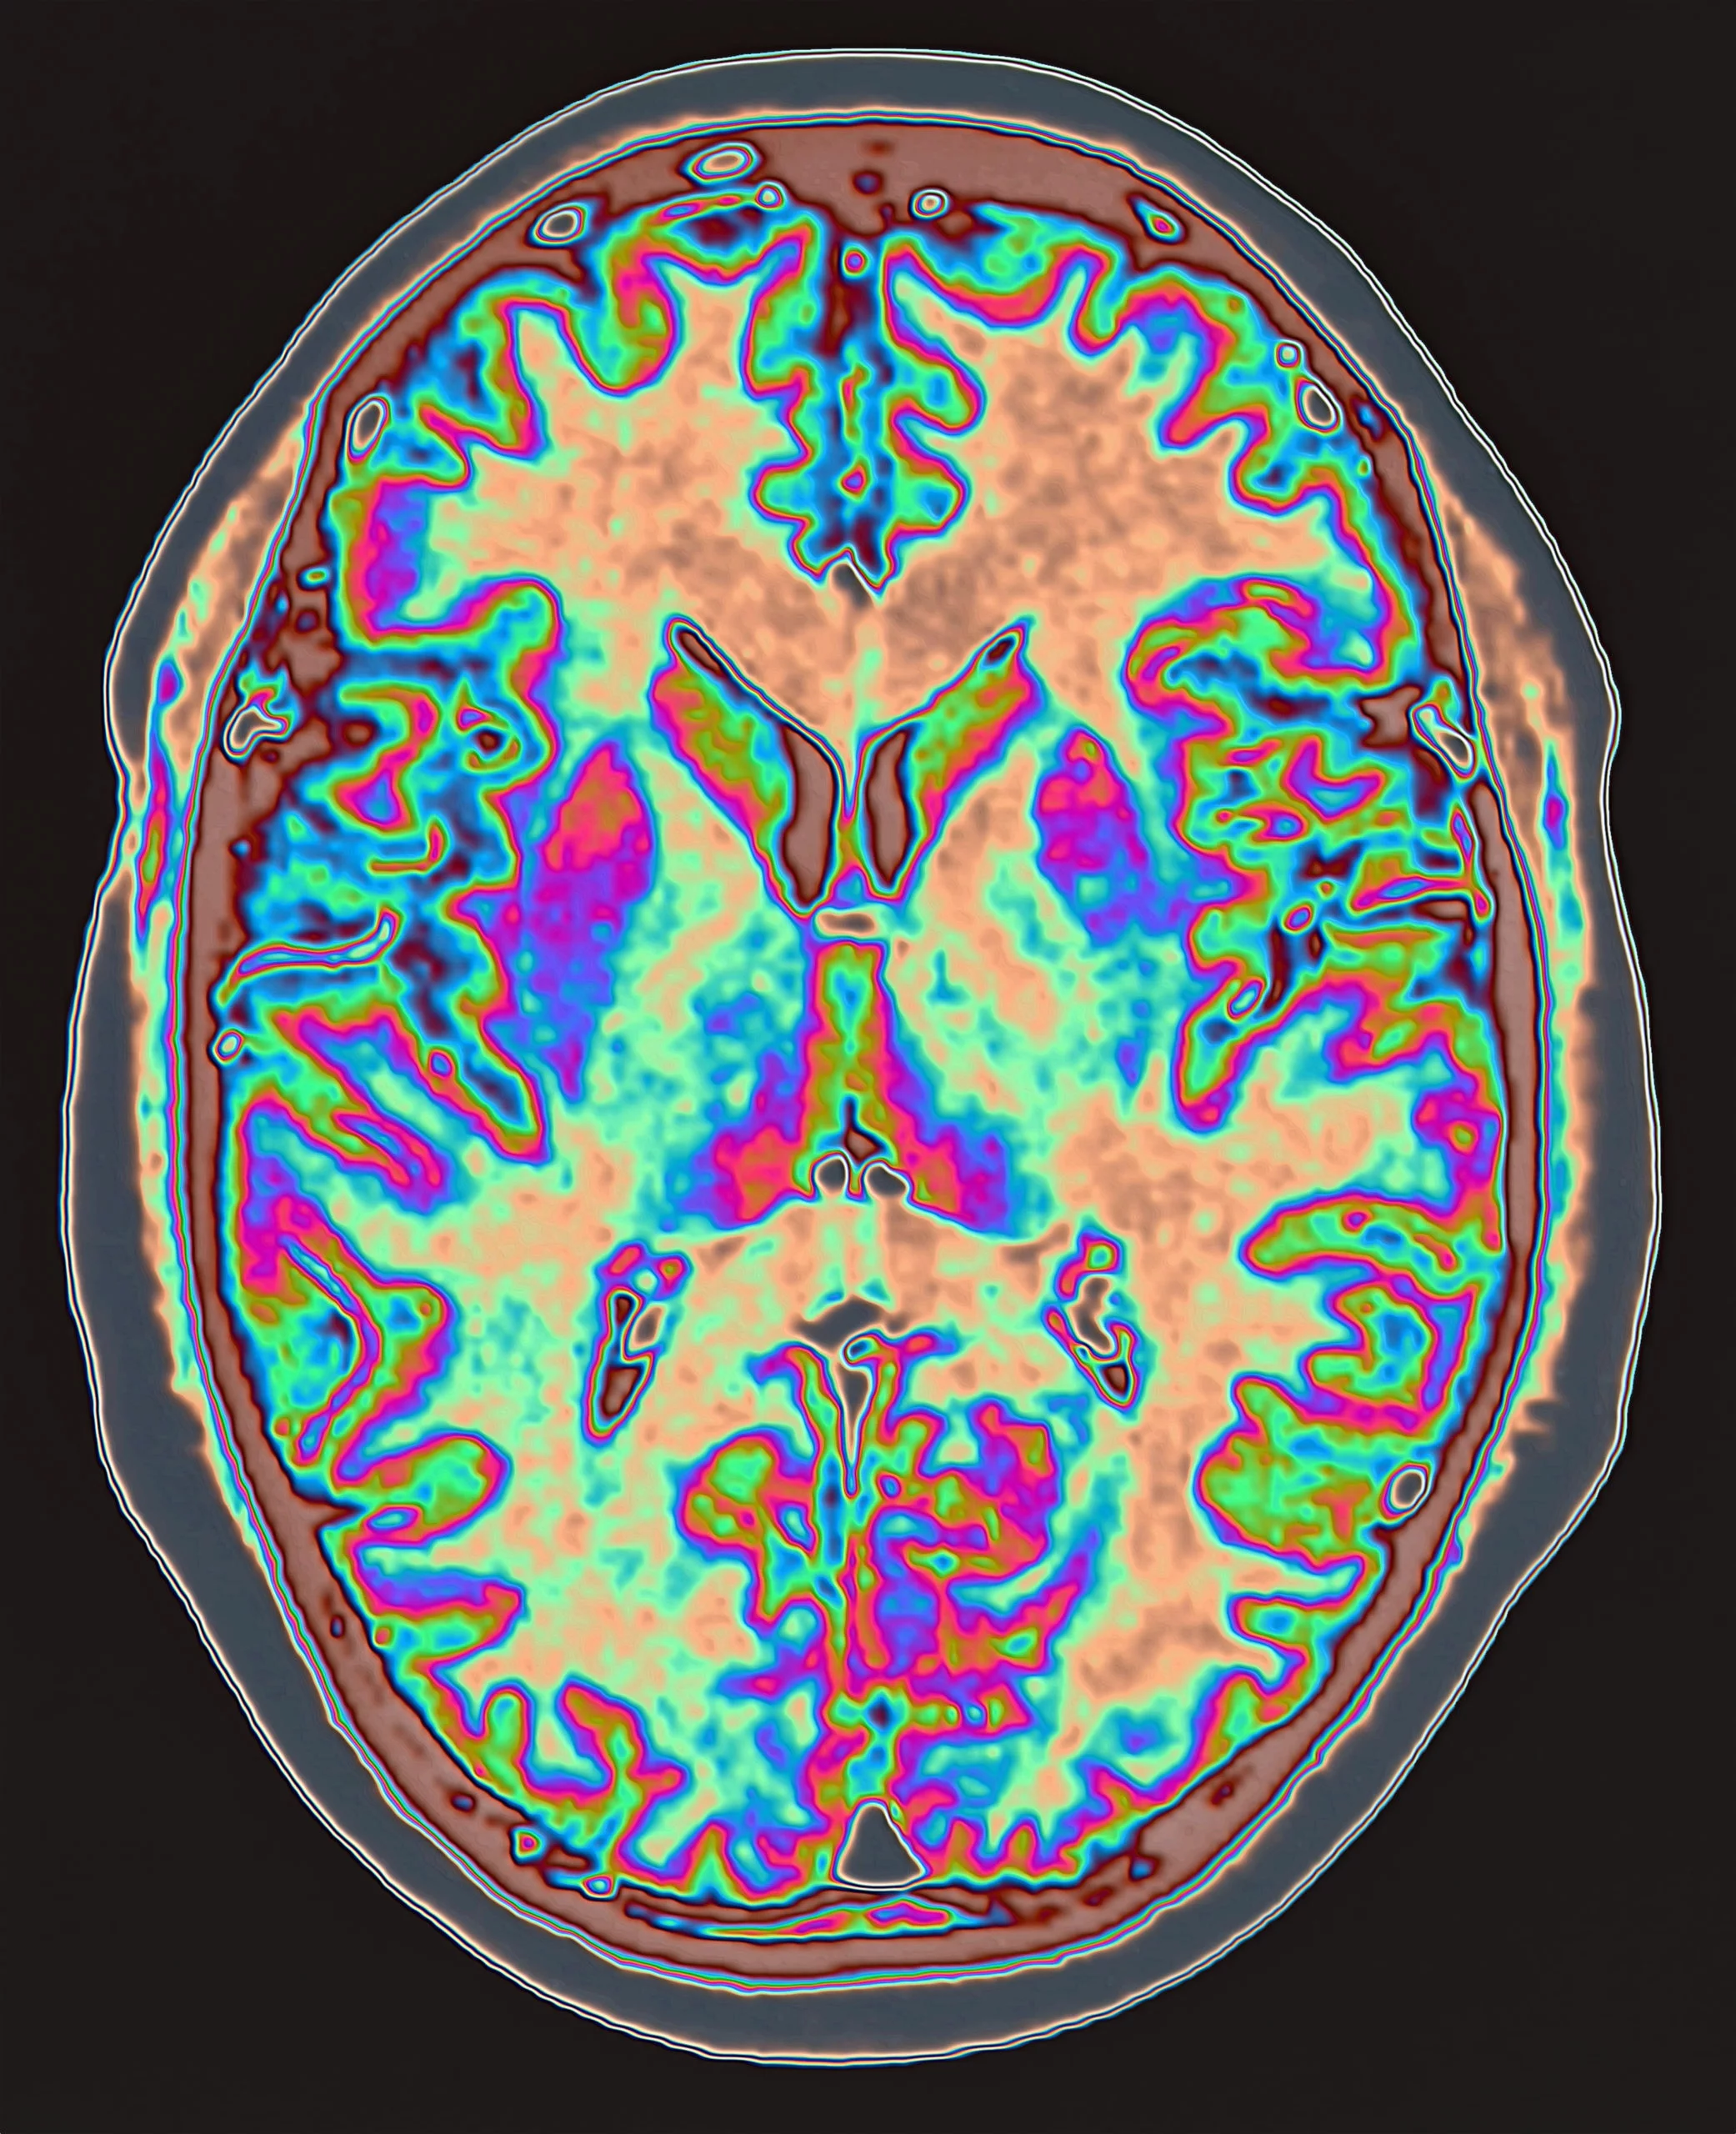

Grâce aux récentes avancées technologiques, les scientifiques peuvent vraiment voir comment l'activité physique profite au cerveau. Ils peuvent mesurer le flux sanguin vers le cerveau à travers le cou, à travers le cerveau, à travers le crâne.